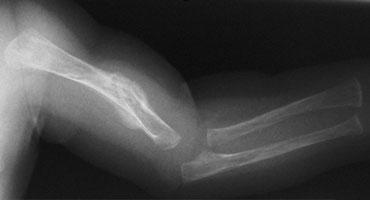

Hai trẻ sơ sinh bị gãy xương đùi. Lạm dụng trẻ em bị nghi ngờ do tuổi của trẻ và bệnh sử không nhất quán được cung cấp bởi cha mẹ.

Gãy xương thân xương (Diaphyseal fractures)

Gãy xương thân xương không đặc hiệu vì chúng có thể xảy ra trong cả chấn thương do tai nạn và không do tai nạn.

Tuy nhiên, trong những trường hợp này, tuổi tác, giai đoạn phát triển của trẻ và bệnh sử lâm sàng rất quan trọng.

Ngã khỏi giường thường không gây ra gãy xương thân xương.

Để gây ra gãy xương thân xương đùi theo chiều ngang, cần phải tác dụng một lực đáng kể.

Gãy xương xoắn là kết quả của lực xoắn vặn.

Mặc dù thường được đề cập, không có bằng chứng nào cho thấy gãy xương xoắn ở chi dưới có độ đặc hiệu cao hơn đối với lạm dụng so với gãy xương chéo hoặc ngang.